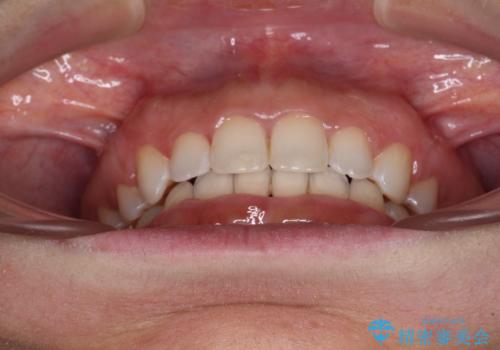

- 口元の突出感と口の閉じにくさを気にして来院された患者様です。

上下左右の小臼歯4本を抜歯し、ワイヤー装置にて口元を引っ込めるよう矯正治療を行うこととしました。

上下顎ともに前突しており、特に上顎は著しい突出感でした。

それでも根気強く通院してくださり、横からの顔貌の印象が大きく改善され、スムーズに口が閉じられるようになりました。